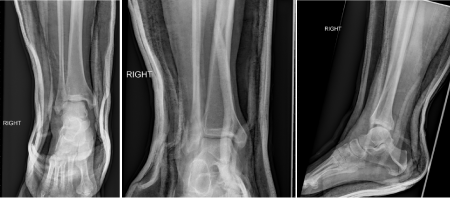

A Sixty-one year old man fell down multiple stairs at his home and sustained an external rotation injury to the right ankle. He was unable to ambulate and had notable deformity of the right ankle. The patient was then taken to the emergency department where he was examined for his injuries. AP, Mortise and Lateral x-rays of the right ankle were obtained. Initial radiographs showed a fracture-dislocation of the right distal fibula with tibiotalar dislocation and a posterior malleolus fracture, the distal fibula being posterior to the tibia. The Bosworth fracture-dislocation was not initially identified radiographically. A radiographical axilla of the medial tibial plafond was visible on x-ray (white arrow in (Figure 1-4)) due to internal rotation of the tibia when the fibula is dislocated posterior to the tibia.9

Figure 1 Mortise, Lateral and AP of initial injury films.

Note: “Axilla” sign on mortise view (white arrow). .